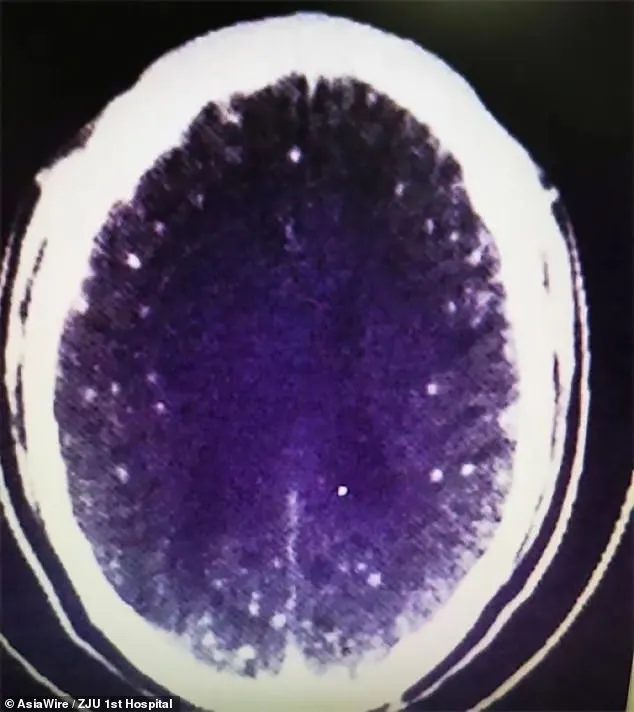

และเมื่อเขาถูกนำส่งโรงพยาบาลในเครือของคณะแพทยศาสตร์มหาวิทยาลัยเจ้อเจียง แพทย์ได้ทำการสแกนสมองและหน้าอก โดยการใช้คลื่นแม่เหล็กไฟฟ้า (MRI) และแพทย์ได้ตรวจพบว่าสมองและหน้าอกของนาย Zhu นั้นเต็มไปด้วยซิสต์ของพยาธิตัวตืดหมู

นอกจากนี้ ดร. หวาง ยังเปิดเผยว่า นาย Zhu ยังมีซีสต์ในปอดและกล้ามเนื้อหน้าอกด้วย คาดว่าน่าจะมีพยาธิตัวตืดบมากกว่า 700 ตัว ในร่างกาย รวมถึงสมองและปอด